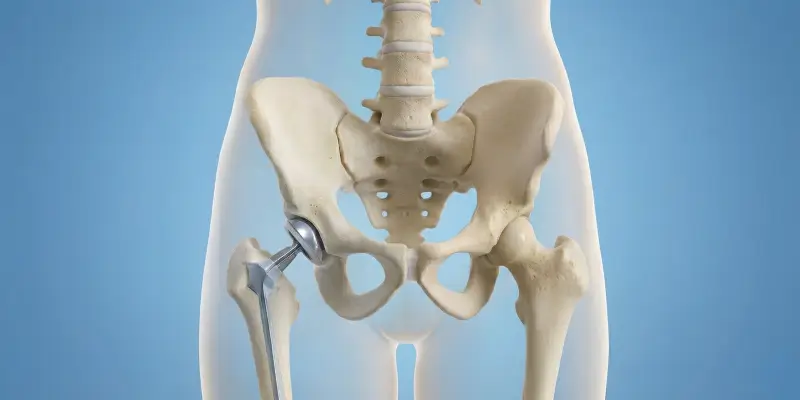

Robotik diz ve kalça protezi, 3D görüntüleme ve robotik rehberlik ile hassas, kişiye özel protez yerleştirmesidir. Avantajlar, endikasyonlar ve rehabilitasyon.